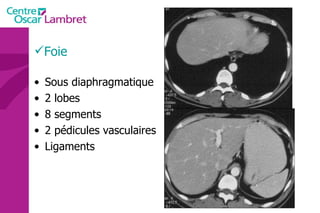

Foie Sous diaphragmatique 2 lobes 8 segments 2 pédicules vasculaires Ligaments

Le foie  pèse entre 1400 et 1600 g et mesure une dizaine de centimètres dans sa plus grande hauteur. L’apport sanguin hépatique est double : par la veine porte  par l’artère hépatique issue du tronc coeliaque.  L’ensemble veine porte- artère hépatique constitue, avec le canal cholédoque un pédicule hépatique.  La ramification de cette veine permet d’isoler 7 segments. Foie